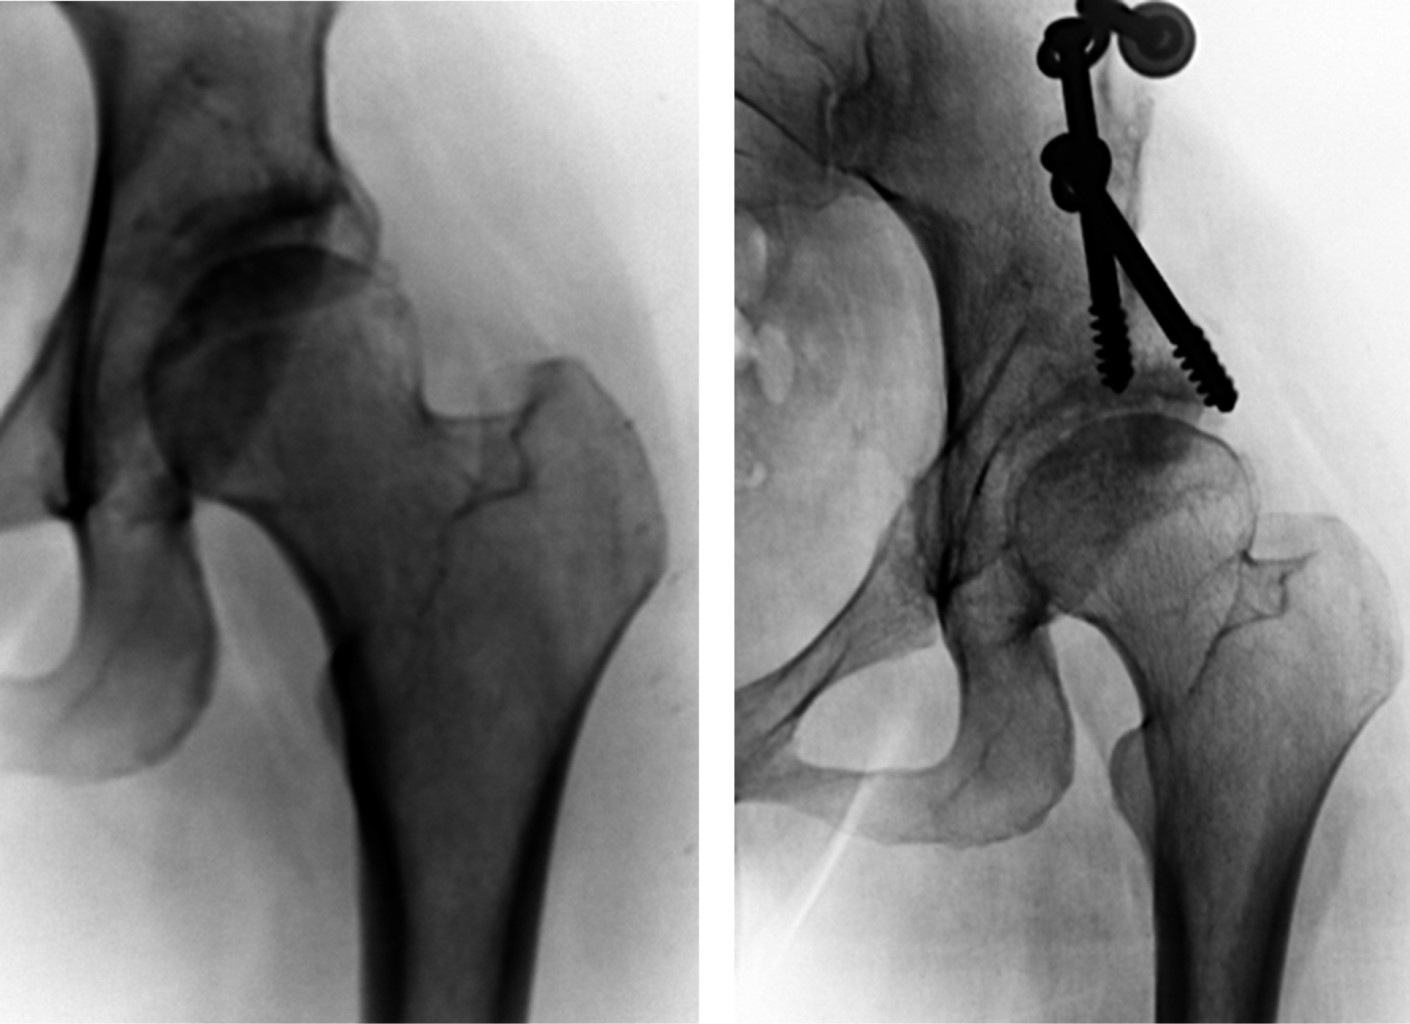

Osteotomías femorales

Lorenz,18 Whitman19 y Colonna,20 entre otros, desarrollaron diversos tipos de osteotomías femorales bajo el fundamento de utilizar el extremo femoral proximal como un vástago, cuyo punto de apoyo se situaba en el acetábulo. Antes de la aparición de los implantes protésicos, estos tipos de osteotomías femorales fueron muy populares. Desafortunadamente, este tipo de cirugías ofrecían malos resultados en movilidad, control del dolor y funcionalidad, por lo que dejaron de usarse.

Como se ha mencionado, un hito en este tipo de tratamientos fueron las osteotomías impulsadas por Friedrich Pauwels. Este autor propuso enfrentar el problema desde un punto de vista biomecánico, conservando, no mutilando la articulación, sólo cambiando la orientación anatómica del extremo femoral proximal con una perspectiva biomecánica de recuperación del cartílago articular.

El recuento histórico de este tratamiento se inicia en 1935 cuando Pauwels21 describe la osteotomía femoral varizante que posteriormente evolucionaría a otro tipo de osteotomías (Figura 1). Este autor fue seguido por Maquet22 y Bombelli,23 entre otros (Figura 2), quienes clasificaron y fundamentaron el tipo de osteotomía que se debería efectuar con fuertes bases biomecánicas.

Estas osteotomías poseen indudable valor en ciertos casos, pero también tienen la desventaja de que la respuesta favorable depende de diversos factores. Destacan entre otros la etiología, el somatotipo que cada individuo presenta como respuesta individual ante la enfermedad, el grado de deterioro articular y el tipo de osteotomía más apropiada para cada caso. Por estas dificultades sus resultados no han podido ser homogéneos, sobre todo en casos avanzados. En últimas fechas y gracias al avance de las aloartroplastías endoprotésicas que ofrecen resultados mucho más homogéneos, ya son pocos los cirujanos que prescriben este tipo de tratamiento como elección primaria para el tratamiento de la coxartrosis; sin embargo, sigue teniendo valor en cirugía profiláctica o en casos con afectaciones incipientes.